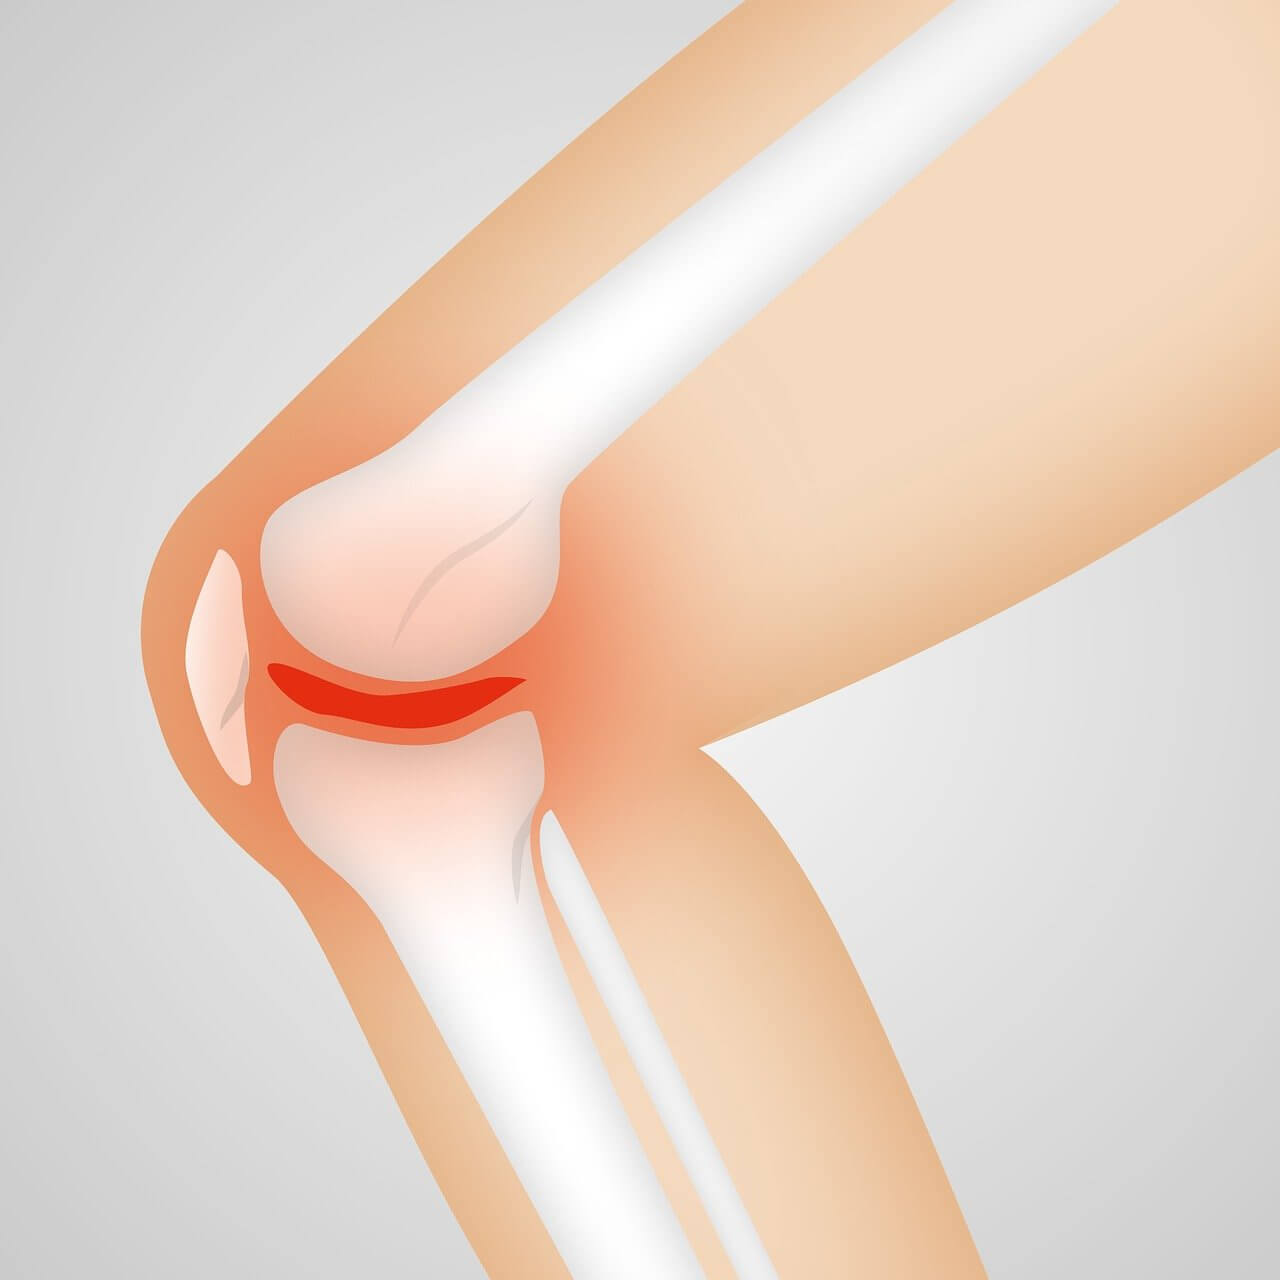

나이가 들어감에 따라 연골의 악화는 종종 관절 통증과 불편함을 유발하여 이동성을 방해하고 전반적인 삶의 질에 영향을 미칠 수 있습니다. 연골의 필수 구성 요소인 콘드로이틴은 뼈 사이의 쿠션 역할을 하여 신체 활동 중 충격을 흡수하는 데 도움을 줍니다.

콘드로이틴은 관절의 뼈 사이에 쿠션을 제공하는 유연한 조직인 연골의 중요한 구성 요소입니다. 나이가 들어감에 따라 우리 몸의 콘드로이틴 양이 감소하여 관절 통증과 뻣뻣함을 유발할 수 있습니다. 콘드로이틴을 보충하면 연골 조직의 유지 및 복구를 지원하여 관절 건강을 개선하는 데 도움이 될 수 있습니다.